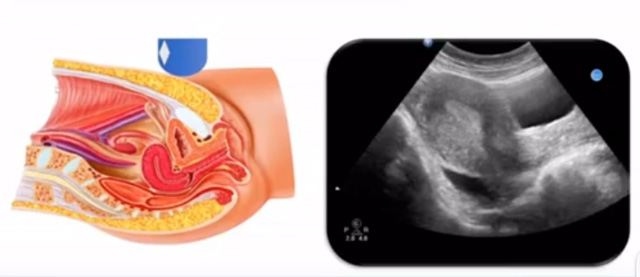

女性生殖系統(tǒng)包括內(nèi)、外生殖器官及其相關(guān)組織以及鄰近器官,其中內(nèi)生殖器是我們超聲檢查的主要對(duì)象。那么內(nèi)生殖器包括陰道、子宮還有輸卵管及卵巢。輸卵管及卵巢稱(chēng)為子宮附件。子宮是倒置梨形,但是它是空腔厚壁肌性器官。它的正常值在育齡婦女。超聲探頭放在貼近腹壁盆腔上面位置,來(lái)看這個(gè)子宮在超聲上面的表現(xiàn)。從輪廓上來(lái)講,和示意圖是一樣的。這就是在超聲上面顯示的一個(gè)子宮的圖片。子宮在不同的時(shí)期與子宮頸的比例。成年婦女指的是育齡婦女為2:1子宮體是比較大的,嬰兒期為1:2說(shuō)明宮頸比較大,絕經(jīng)期1:1。所以我們?cè)诳吹阶訉m圖時(shí)候可以根據(jù)宮體宮頸比例大致可以推測(cè)屬于哪個(gè)時(shí)期的婦女。另外還可以根據(jù)比例大小來(lái)推斷是一個(gè)正常子宮還是異常子宮。

子宮從外到內(nèi),漿膜層、肌層、粘膜層。宮體部宮頸為梭形結(jié)構(gòu)。宮腔為上寬下窄的三角形,連接為峽部。子宮有什么功能呢?月經(jīng)血產(chǎn)生跟排出通道,精子運(yùn)行通道受精作用。囊胚著床及胎兒發(fā)育、生長(zhǎng)的場(chǎng)所。分娩時(shí)產(chǎn)生宮縮使胎兒、胎盤(pán)娩出。未孕的子宮是很小的,已孕子宮就非常大,平均胎兒都有6斤重。所以這個(gè)后壁就體現(xiàn)出來(lái)。輸卵管由子宮角部向外延伸,為一對(duì)細(xì)長(zhǎng)而彎曲的管道,呈管狀中空結(jié)構(gòu),大概長(zhǎng)度是8-14厘米,粗1-4毫米,它的下方為卵巢和闊韌帶。間質(zhì)部是厚一點(diǎn)的,峽部是比較窄的地方,壺腹部,漏斗部。正常情況下,輸卵管在普通超聲DR難以顯示。